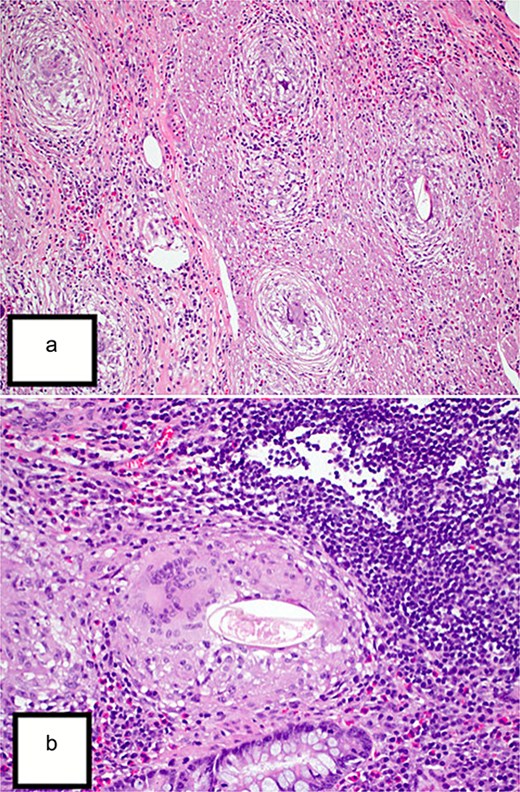

Final histopathological examination revealed the appendix shows diffuse mucosal and focally transmural granulomatous inflammation surrounding Bilharizial ova (Fig. 1a and b).

(a) Hematoxylin and eosin (H&E) stain (10×) revealed the appendix shows diffuse mucosal and focally transmural granulomatous inflammation surrounding Bilharizial ova. (b) H&E stain (40×) revealed the appendix shows diffuse mucosal and focally transmural granulomatous inflammation surrounding Bilharizial ova.